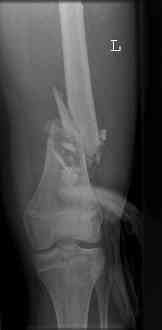

16 yr old boy, high energy motorcycle trauma trauma in July 2005 with:

- hip dislocation + acetabular fracture L

- distal femoral fracture L

july 05: LISS femur, LCP plate tibia, double recon. plate post. acetabulum

nov 07: persistant non-union distal femur; other fractures healed

uneventfully.